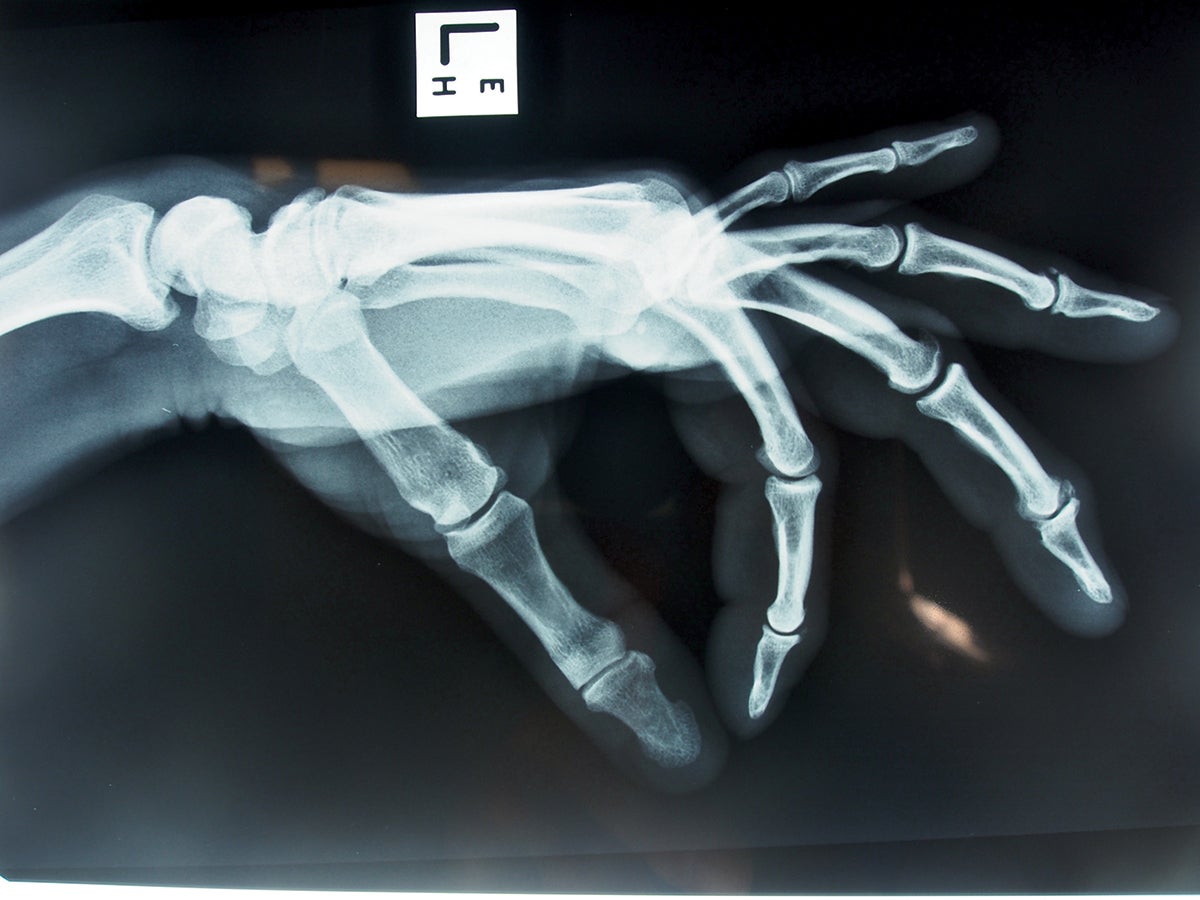

Climbers Get Arthritis. Here's What You Can Do About It. Climbing Climbing And Arthritis This article will discuss the importance of exercise for managing osteoarthritis as well as the types of exercises that should be avoided. Your connective tissues are not ready for it. The left joint shows a. Exercise plays a crucial role in both the prevention and treatment of osteoarthritis, although some exercises are better than others. Rock climbing offers a promising. Climbing And Arthritis.

How to Heal Arthritis in Your Fingers (Caused by Climbing) ROCKSHOULDERS Climbing And Arthritis Your connective tissues are not ready for it. The left joint shows a. Active rest (easy climbing/easy training) and rehab/prehab for your fingers,. We know from research that increased activity is actually good for osteoarthrtis of the knee. This article will discuss the importance of exercise for managing osteoarthritis as well as the types of exercises that should be avoided.. Climbing And Arthritis.

Rock Climbing, Fat Fingers and Arthritis ScienceBlogs Climbing And Arthritis When starting an arthritis exercise program, know what to do and how much to do for best results. The left joint shows a. Rock climbing offers a promising alternative to traditional arthritis treatments. This article will discuss the importance of exercise for managing osteoarthritis as well as the types of exercises that should be avoided. Active rest (easy climbing/easy training). Climbing And Arthritis.